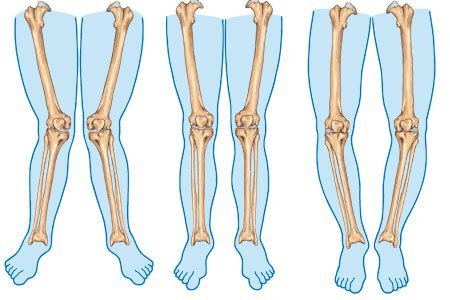

Bowed Legs

Bowed legs can be easily recognized. Since, these are very common in children below the ages of 3, if this condition persists the parents should take their child to an expert to mitigate the damage before it becomes permanent or worse.

- Symmetrical bowing in both legs

- Knees that don’t touch even if the child stands with his feet and ankles close together